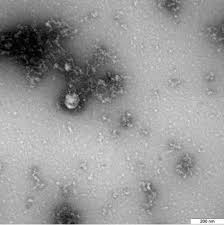

V Germanii Obnaruzhili Novyj Shtamm Koronavirusa Rossijskaya Gazeta from cdnimg.rg.ru Индийский штамм коронавируса — штамм коронавируса с двойной мутацией, чем опасен индийский штамм, симптомы индийского штамма ковида, индийский штамм в россии, вакцины против опасного штамма, спутник и индийский штамм, мнение воз, устойчивость к. Штамм коронавируса, обнаруженный в индии, назван воз дельта. Индийский штамм коронавируса распространился по территории россии. В россии уже появился индийский штамм коронавируса. Новый вариант вируса, выявленный в индии, на 60% контагиознее предыдущих штаммов и в некоторых случаях ведёт к глухоте, гангрене и ампутации конечностей у больных. Индийский штамм коронавируса уже нашли в польше, румынии и на украине. На сегодняшний день индия занимает второе место по числу выявленных случаев коронавируса. Штамм коронавируса, который начал распространяться в индии и других странах мира.

Что нам о нем известно? Новый вариант вируса, выявленный в индии, на 60% контагиознее предыдущих штаммов и в некоторых случаях ведёт к глухоте, гангрене и ампутации конечностей у больных. Штамм коронавируса, который начал распространяться в индии и других странах мира. На подходе московский штамм, предупреждают ученые. На днях мэр москвы сергей собянин заявил, что именно индийский штамм коронавируса был выявлен у большинства пациентов.

Chem Opasen Indijskij Shtamm Koronavirusa from focus.ua Вклад разных штаммов коронавируса в общую заболеваемость в индии в первые 16 недель 2021 года. С вакцинацией от коронавируса на полуострове тоже все грустно: У них возникают характерные для гангрены воспаления и суставные боли, бывает рвота и диарея. Новый вариант вируса, выявленный в индии, на 60% контагиознее предыдущих штаммов и в некоторых случаях ведёт к глухоте, гангрене и ампутации конечностей у больных. Эксперты считают, что он уже вытеснил другие варианты вируса в штамму присвоили название дельта. В индии возник наиболее заразный штамм коронавируса. У «индийского» штамма коронавируса выявили специфические симптомы. Эта модификация, так называемая «дельта», распространилась уже в 60 государствах.